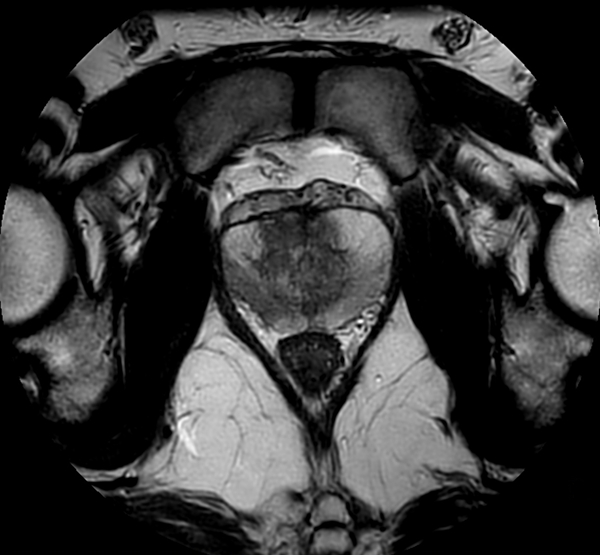

Motion-free Prostate imaging

Used Solution